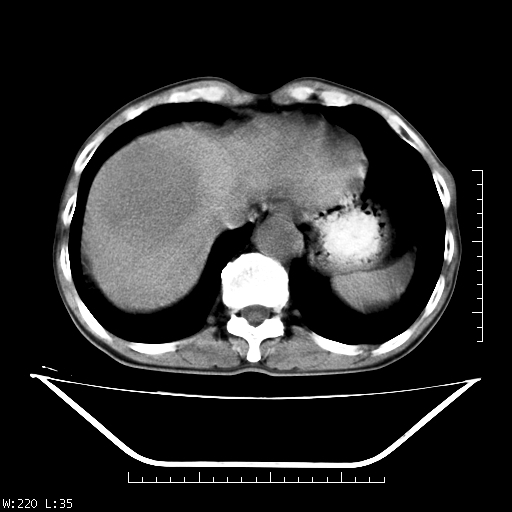

男,70,右上腹痛两月,有乙肝病史,b超提示肝占位,ct如下,请会诊。

补充:该患者afp9.24

肝右叶类圆型密度减低影,密度不均,边界清晰其内可见更低密度影,腹膜后可见小淋巴结肿大,增强扫描动脉期病灶明显强化,静脉期及延时扫描见强化不明显,快进快出表现。

1.肝右叶低密度影考虑为肝癌;

2.肝转移待除外。

平扫呈低密度占位,动脉期斑片状明显强化,病灶边缘清晰,见假包膜;门脉期呈低密度,符合肝癌快进快出强化特征

补充:该患者afp 9.24,似乎与原发性肝癌不符合,另胰头区结构正常吗?请大家继续发表高见。